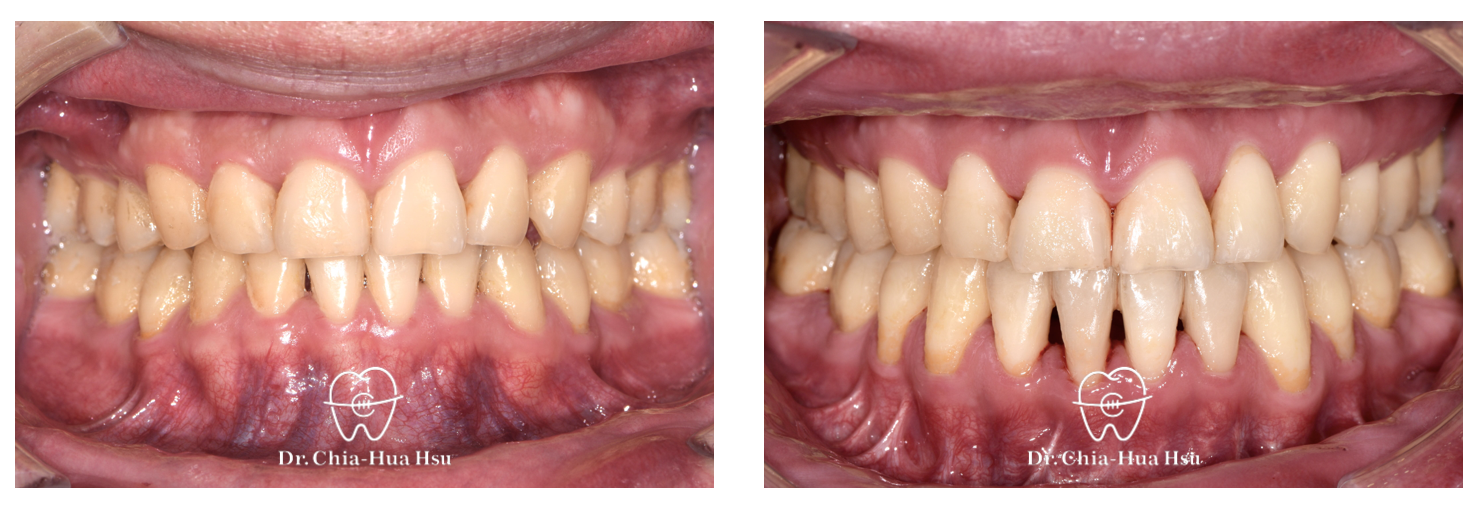

• 有在長期重訓的張先生,年輕時做過矯正,不過因為患者下顎後縮(小下巴)先天構造上呼吸道比較狹窄,隨著年紀漸增以及增肌過程體重增加,進而導致患者出現嚴重的睡眠呼吸中止症,患者嘗試過正壓呼吸器但是戴不住,因而尋求正顎手術治療。

• 病患主訴:下顎後縮、睡眠呼吸中止、二級骨性咬合不正。

• 問題分析:患者是標準的骨骼二類咬合(Skeletal Class II),下巴後縮、有睡眠呼吸中止症以及齒列不正。

• 治療方式:使用傳統金屬矯正器,合併正顎手術(雙顎),以手術方式將下顎骨前移改善呼吸道與外觀。

• 治療結果:齒列排齊,睡眠呼吸中止症改善許多,臉型變長、下巴輪廓也較明顯。